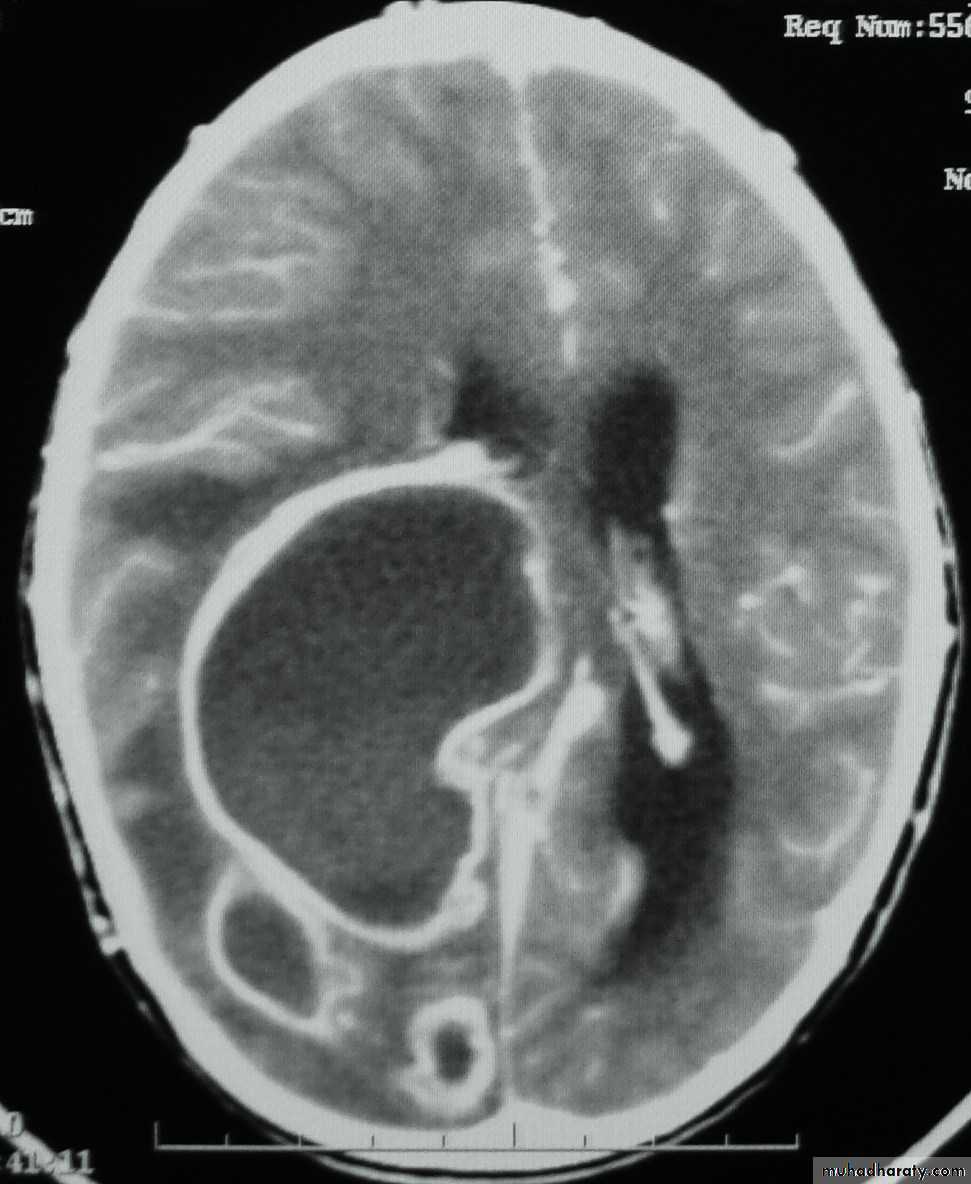

Brain Abscess CT with contrast

• They will show a single (or multiple) space occupying lesion that is well delineated with an enhancing wall, with variable surrounding oedema.